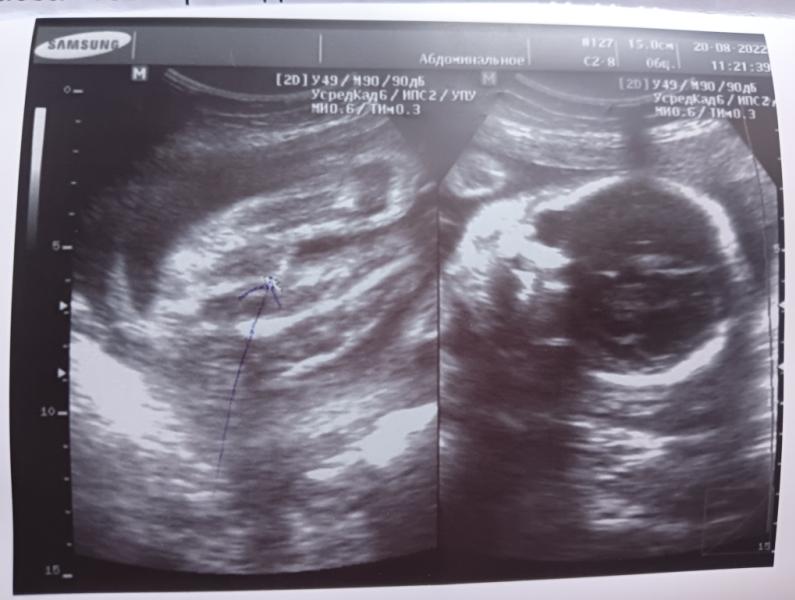

Сделали узи, врач сказал мальчик, я правда на фото кроме лица ничего не вижу, но он мне даже стрелочкой нарисовал где писюн)) Футбольная команда ждет пополнения. )))

Я теперь тоже танчик вижу. 😁

Там же все видно достоинства мужчина растёт в утробе